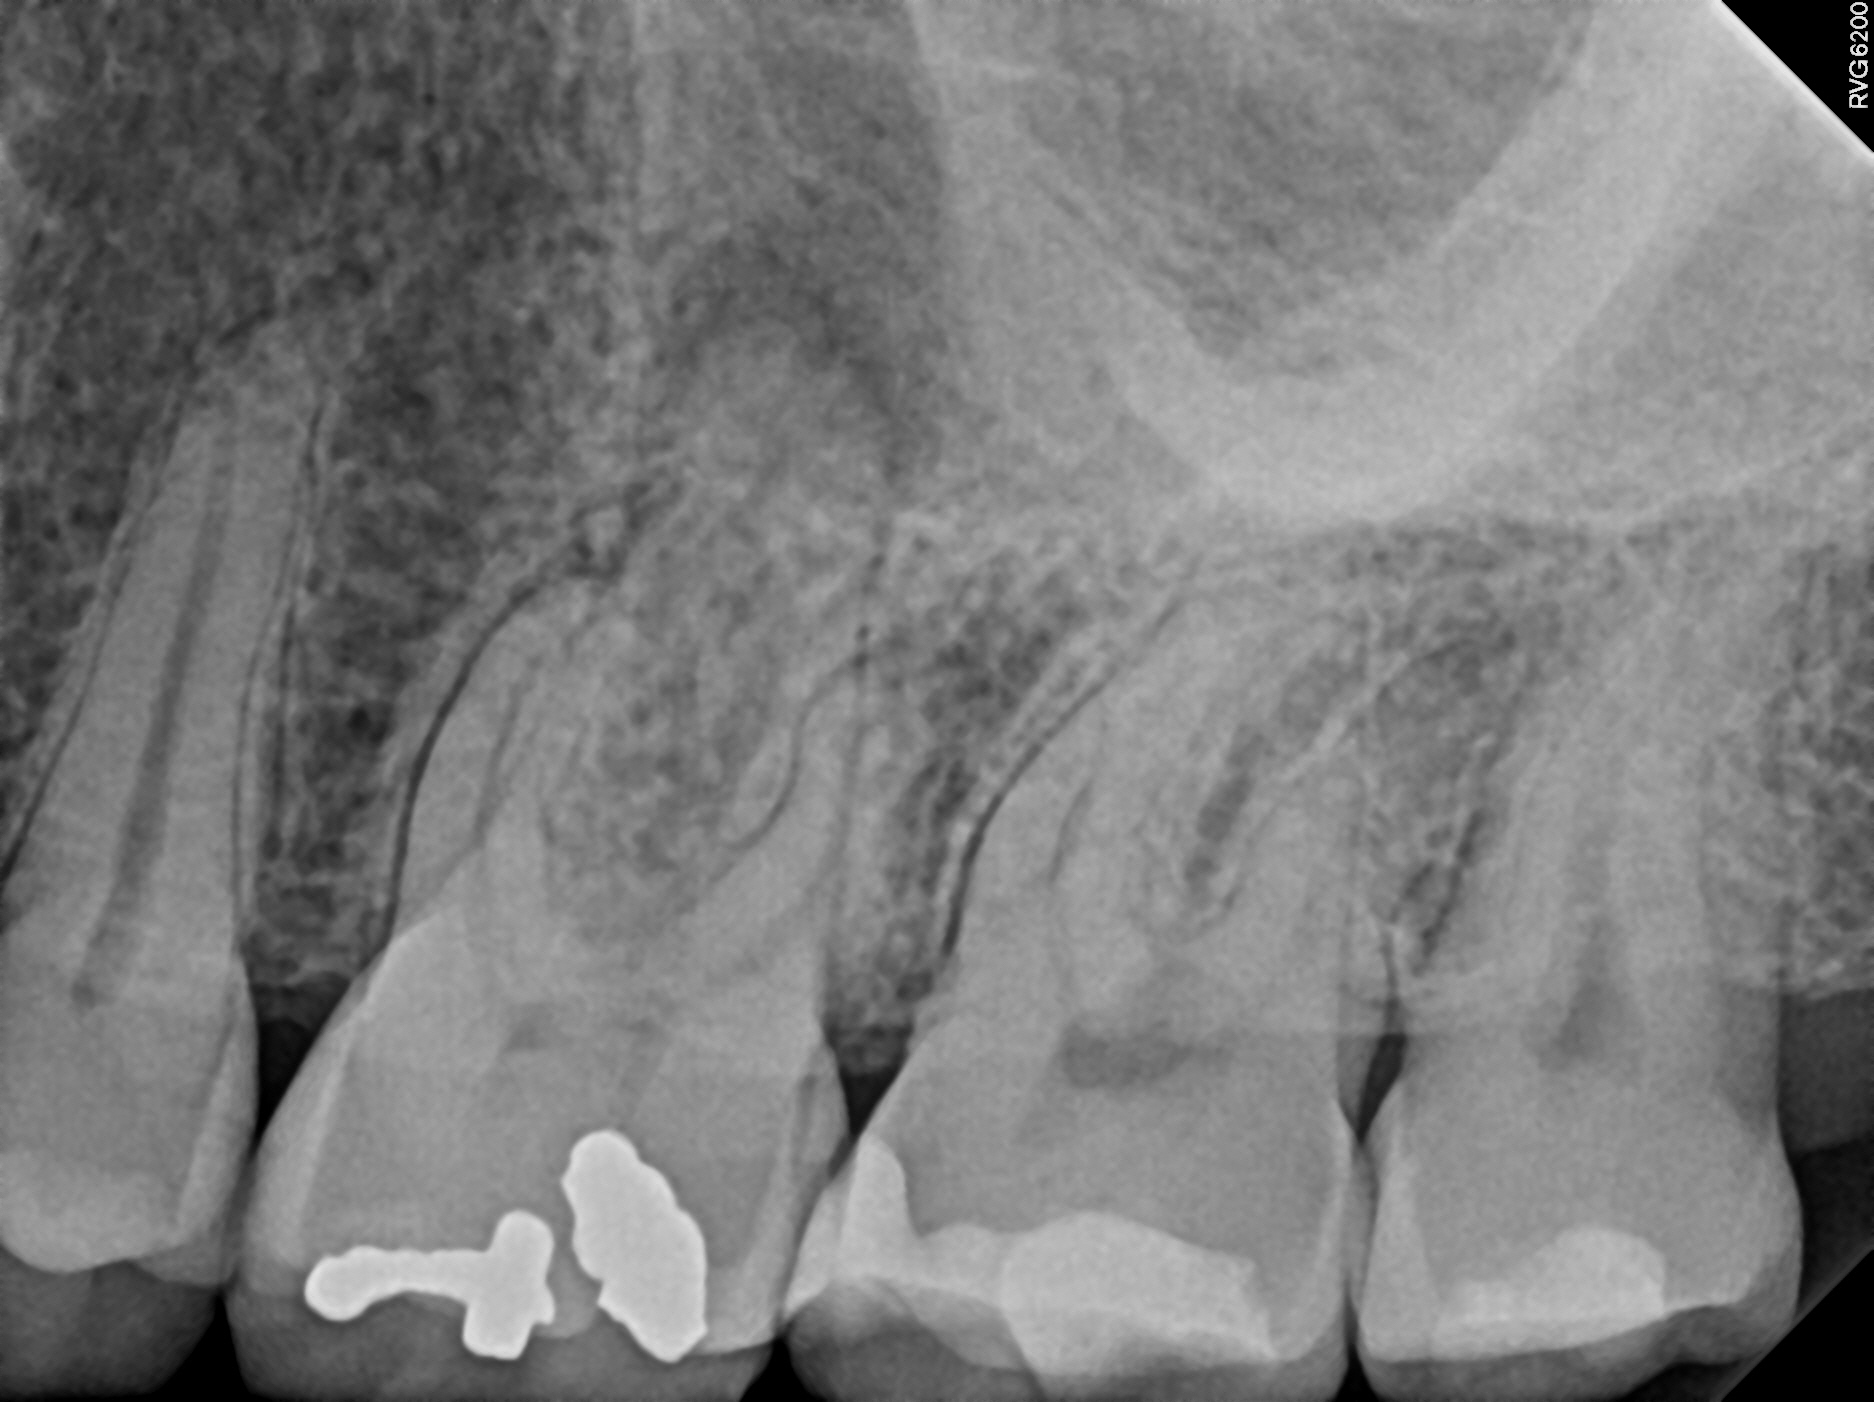

Case 5

Another case showing dramatic healing from root canal treatment. This patient had chronic sinus inflammation that never seemed to heal. The cause--an infected tooth. The top row images show both an erosion of the sinus floor from the tooth roots into the sinus cavity, as well as significant inflammation (swelling) of the sinus soft tissues that line the sinus. During retreatment I was able to find and clean all the canals, including one canal that was previously missed during the first root canal (I did not treat the original root canal). The bottom row images (one year later) shows complete re-establishment of the sinus floor (the bone that separates the sinus from the teeth) and complete resolution of the sinus swelling. There is no more infection. This retreatment case shows that even if a root canal treatment has failed, it can still often be saved. Always seek evaluation from an Endodontist before pulling out a "failing root canal"!